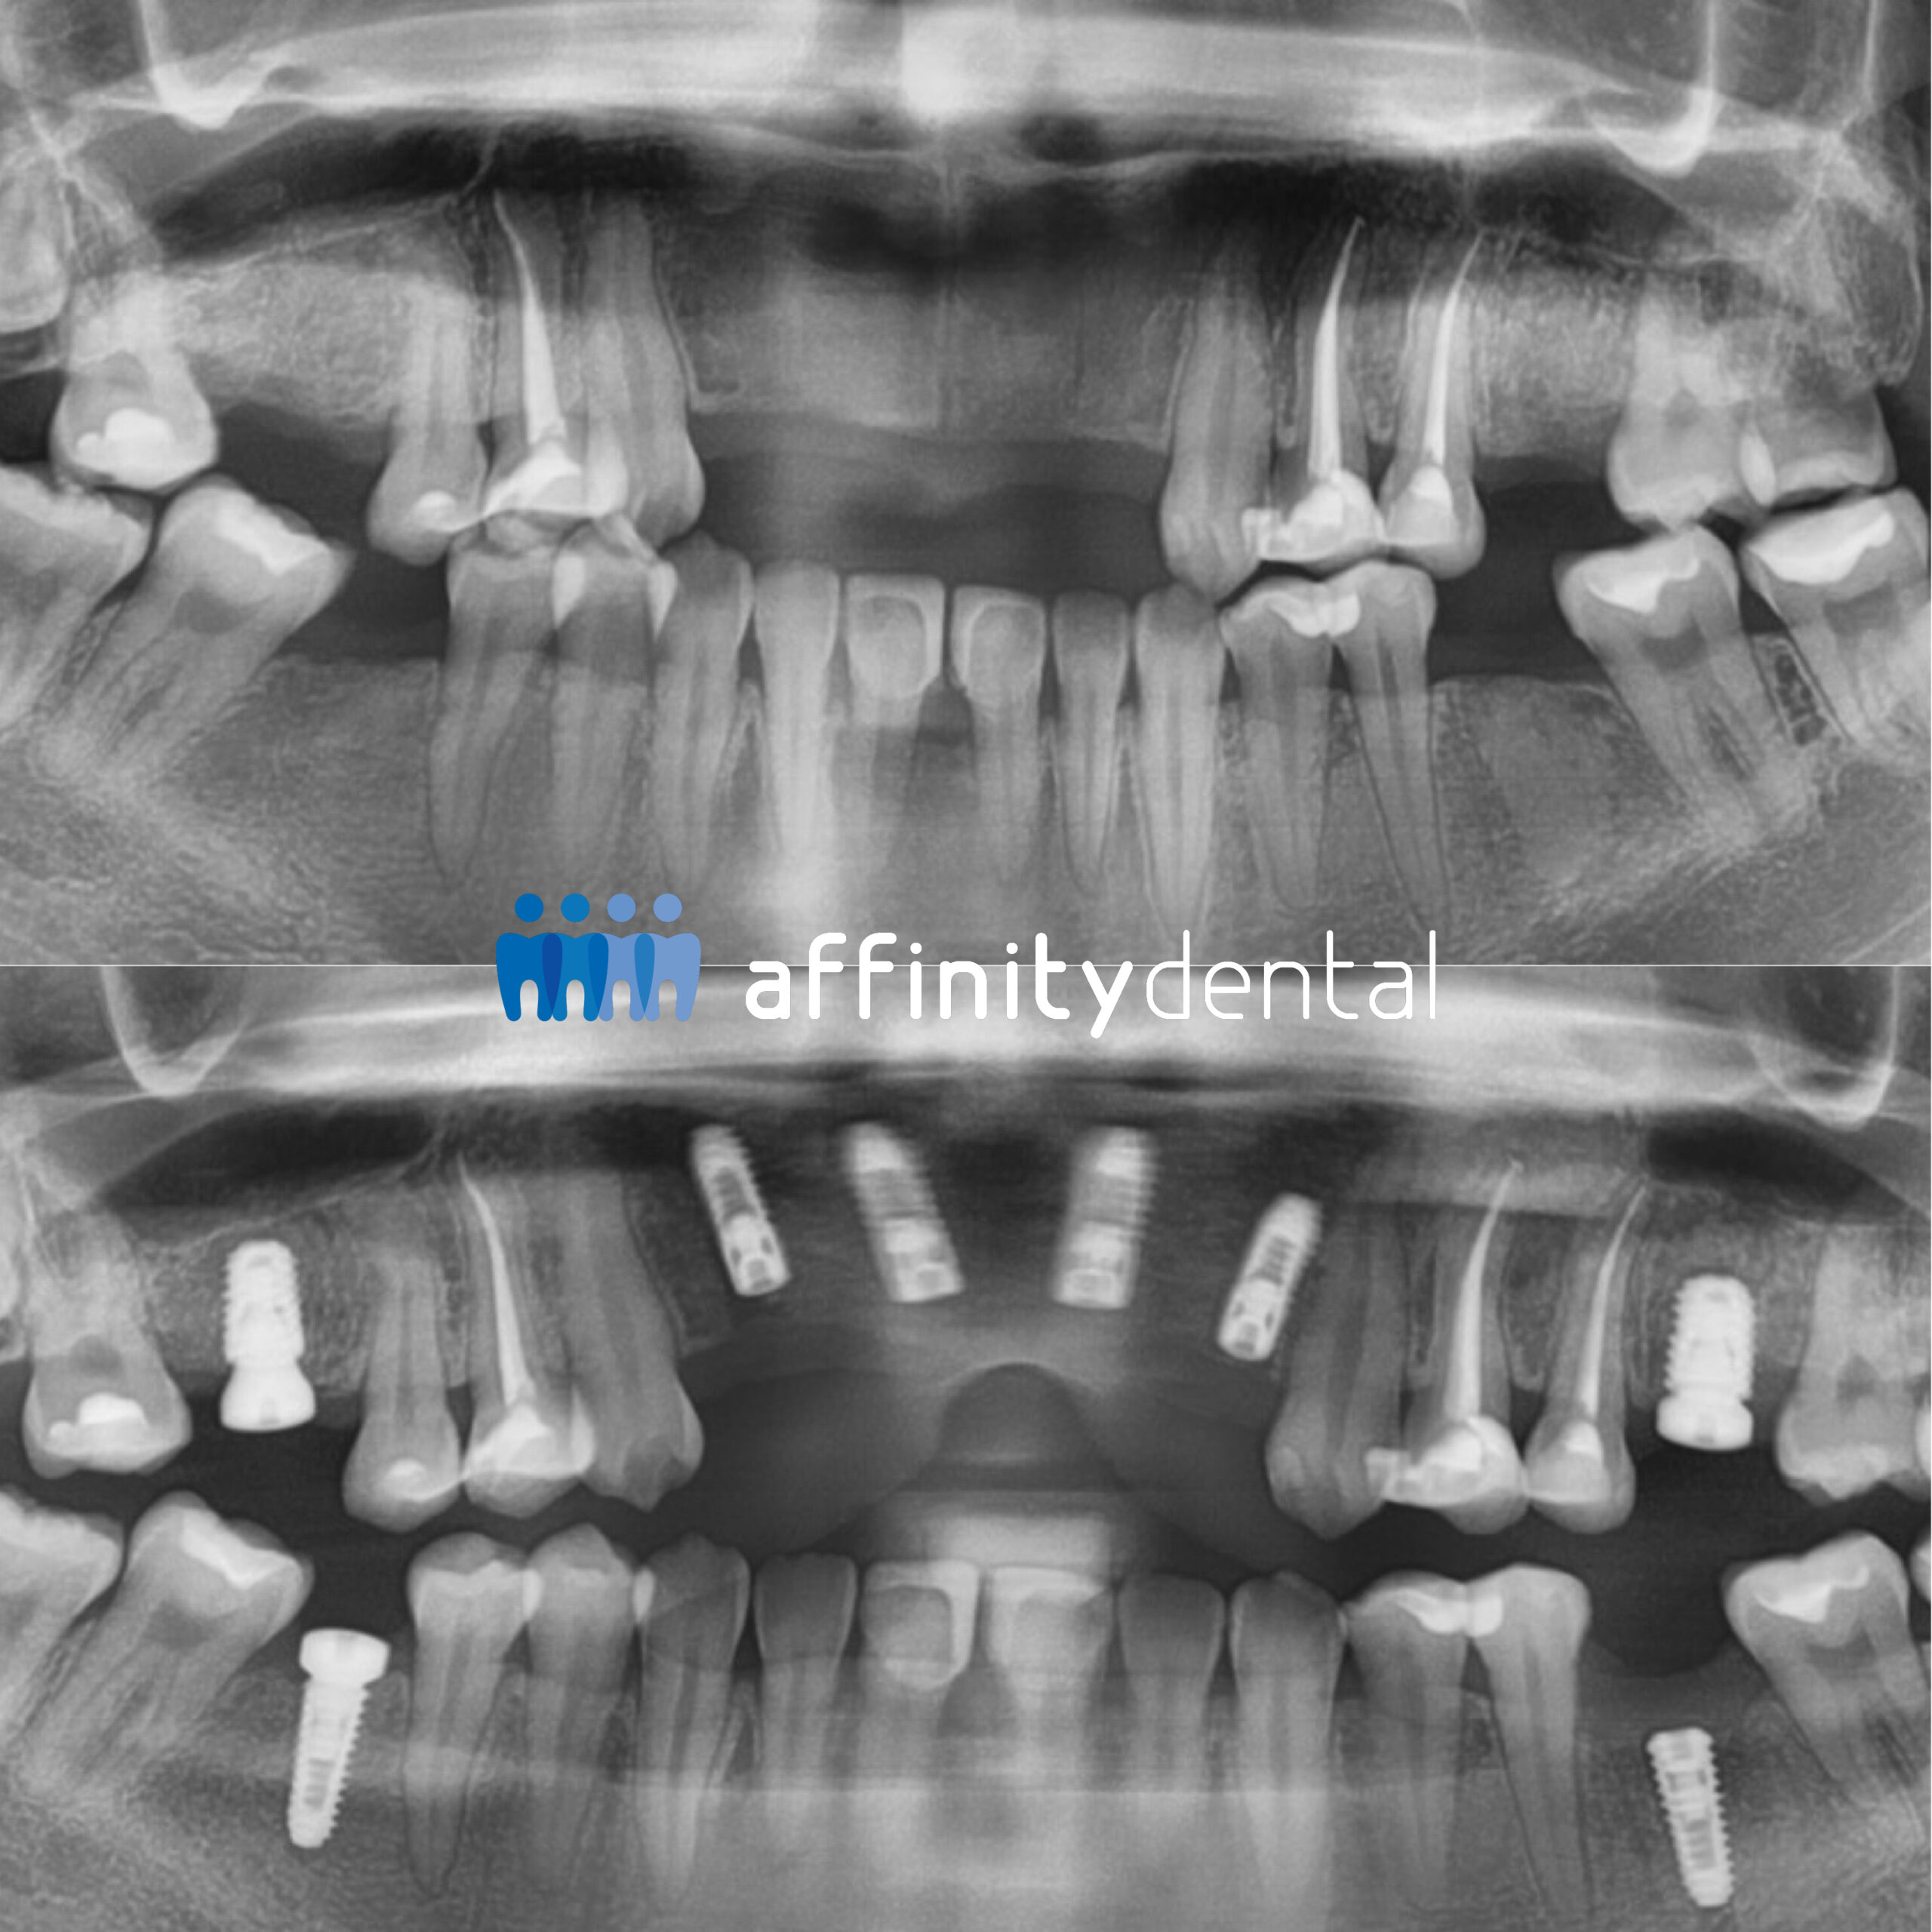

“1 year and 8 months of a significant dental restoration project, involving lots of implants, many of them only after grafting to restore receded bones. Dr. Jerome and his team did a tremendous job, always punctual, professional, precise, patient, never accepting less than perfect. If I had any suggestions how to improve the result they would not hesitate to implement that — but it’s just perfect. It was not cheap, but compared to other offers absolutely reasonable for this amount of professional effort. Wishing Dr. Jerome and the whole team all the continuing success they deserve for their great work!”

Matthias’s story highlights what this article emphasizes: implants are not cheap, but they are reasonable when viewed against the expertise, technology, and effort required. His experience reflects how phased treatment, advanced grafting, and meticulous care translate into long-lasting and life-changing results.